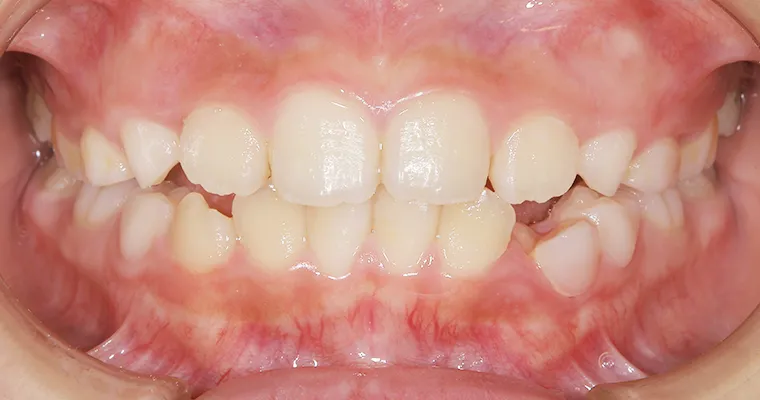

CASE.3 歯並びが悪い

正面観

AFTER

| 主訴 | 歯並びが悪い 乳歯と永久歯が重なっている 歯がまっすぐはえてこない |

|---|---|

| 治療期間 | 6-7ヶ月 |

| 治療費 | 440,000円(税込) ※調整、器具、治療後にお渡しするEFLine(矯正後の後戻りを防ぐ器具)も全て込みでの金額となっております。 |

| 治療内容 | 拡大床矯正 EF Lineで筋機能療法 |